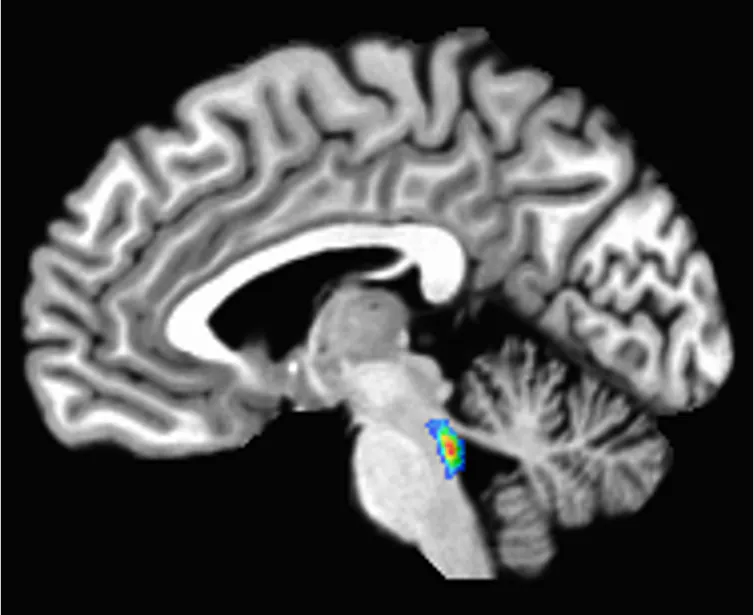

El locus coeruleus se encuentra en el tronco del encéfalo, la parte más baja del cerebro. Su nombre, "mancha azul", proviene de un pigmento llamado neuromelanina producido por sus células.

Locus coeruleus, que significa "mancha azul", se encuentra en el tronco del encéfalo, la parte más baja del cerebro. Elizabeth Riley, CC BI-SA